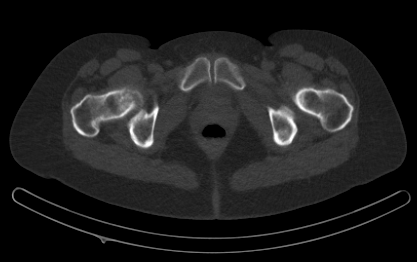

- Strahlung wird mit entsprechenden Geräten sichtbar gemacht (SPECT [SinglePhotonenEmissions ComputerTomograph] oder PET [PositronenEmissionsTomograph]).

Radiologie

- Darstellung des Aussehens von Strukturen.

- Nutzung verschiedene Techniken wie z. B. Ultraschall, konventionelles Röntgen, Computertomographie (CT) oder Magnetresonanztomographie (MRT).

- im Falle des konventionellen Röntgen oder des CT wird Strahlung von außen (Röntgenröhre) durch den Körper "geschickt" und auf der anderen Seite aufgenommen (Detektor).